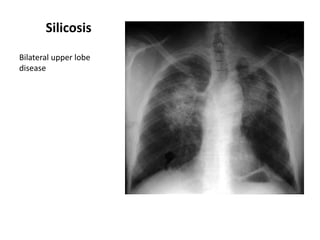

Silicosis

Bilateral upper lobe

disease